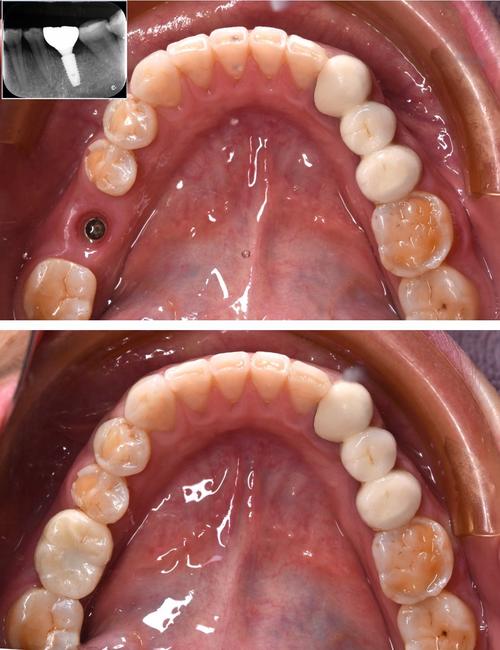

- 案例: 要求查看医生过往的种植牙案例(尤其是和你情况类似的),了解效果。